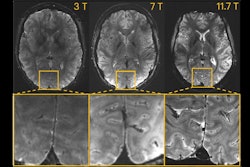

In one experiment, the group imaged three subjects using three different MRI scanners configured with exactly the same parameters and compared the images. The differences are clear, and it’s a “no brainer” that 11.7 tesla reveals superb brain details, Boulant said.

Caption: T2*-weighted 2D GRE acquisitions at 3T, 7T, and 11.7T (different volunteers). Sequence parameters : FA = 27°, TR = 600 ms, TE = 20 ms, resolution = 0.2 × 0.2 × 1 mm3, GRAPPA = 2, bandwidth = 40 Hz/px, TA = 4 min 20 s. Acquisitions were performed with 1 (body coil) Tx-32Rx, 8Tx-32Rx, and 8Tx-32Rx head coils at 3T, 7T, and 11.7T respectively.Image courtesy of Nicolas Boulant, PhD